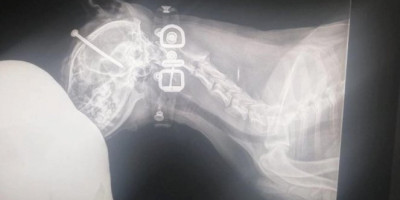

Pas sa ekserom dužine od pet centimetara zakucanim u glavu pronađen je sinoć u novosadskom naselju Satelit, a slučaj zlostavljana životinje prijavljen je policiji.